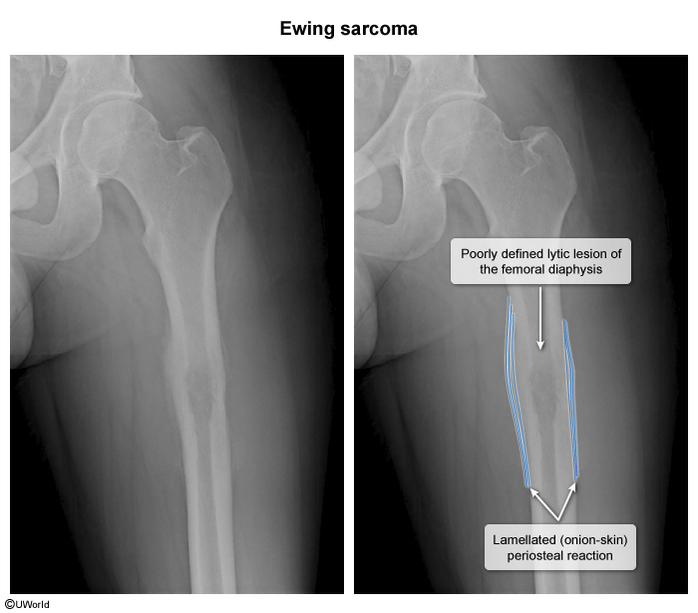

ewing sarcoma